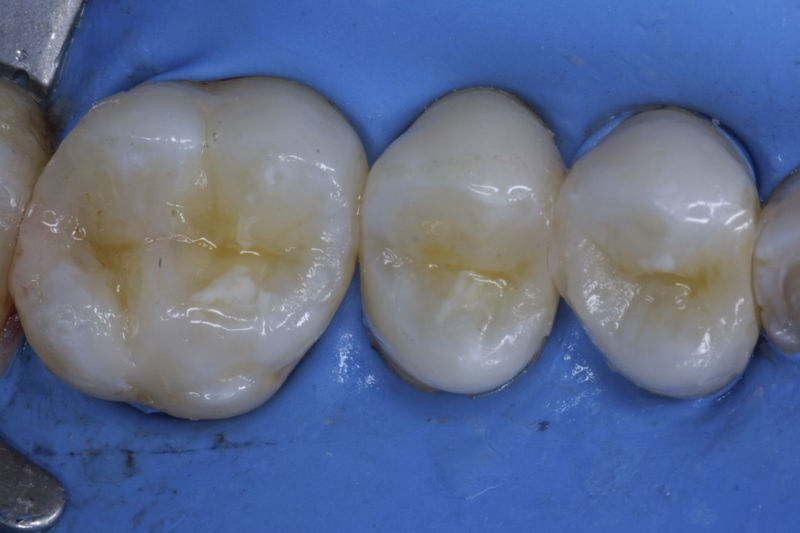

Restauraciones fabricadas en el laboratorio con materiales estéticos, los cuales cubren de manera parcial dientes posteriores. Se utilizan primariamente para restaurar dientes con caries, fracturas y/o defectos amplios. Para poder enviar el caso al laboratorio se toman impresiones utilizando materiales de impresión o técnicas modernas digitales.

Disciplina fundamental de la Odontología enfocada en el diagnóstico, prevención y tratamiento restaurador de las piezas dentales que han sufrido daños. Su objetivo principal es devolver al diente su equilibrio biológico, funcional y estético cuando su integridad ha sido alterada. Resinas directas, incrustaciones, coronas.